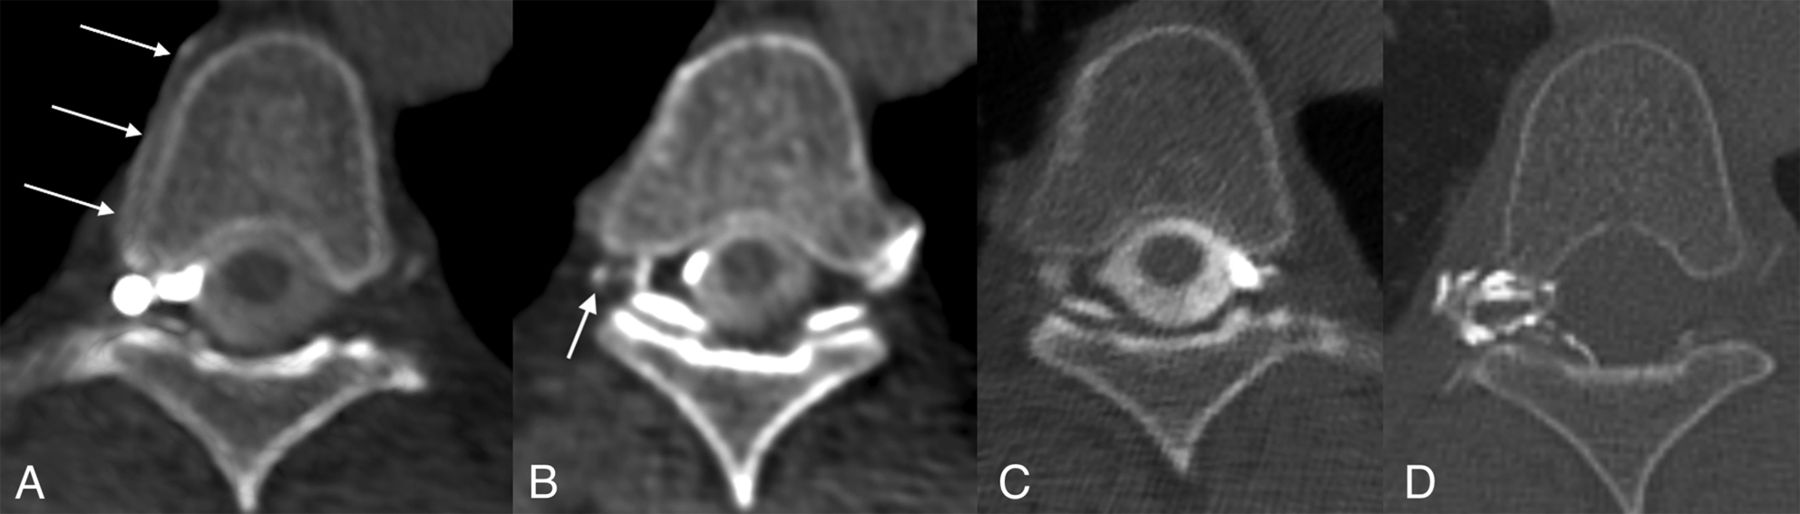

Left T5 CVF with contralateral venous drainage and subsequent treatment. A, Axial right lateral decubitus CTM image shows dependent layering of contrast on the right side of the subarachnoid space but no leak. B, Axial left lateral decubitus CTM image shows more uniform distribution of contrast within the subarachnoid space following turning of the patient but also abnormal left radicular veins opacified by dense contrast (dashed arrow) and a hyperdense right paravertebral vein (arrow). C, Axial left lateral decubitus CTM MIP image shows transvertebral intraosseous drainage of the CVF to the right side (arrow). D, Axial posttreatment CT shows contrast-opacified fibrin sealant filling the foramen (arrow) and extending into the epidural space of vertebral canal.